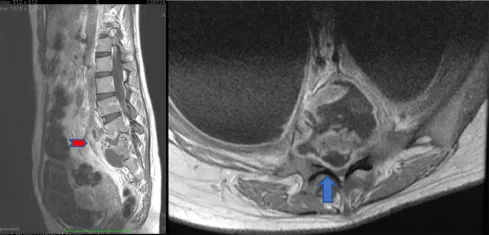

- Tuberculous Spondylitis (Pott's Disease)

- Site: Thoracolumbar spine.

- Features: 'Cold abscess', psoas abscess, gibbus deformity.

- Paradoxical reaction. ATT: 9-12 months.

⭐ > Pott's disease (tuberculous spondylitis) most commonly affects the lower thoracic and upper lumbar vertebrae, and can lead to characteristic 'cold abscesses' and kyphotic deformity (gibbus).